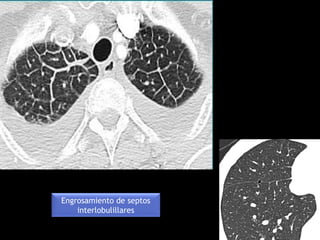

• Numerosos septos interlobulillares claramente visibles indican

con frecuencia patología intersticial (en condiciones normales

vemos algunos)

• Traducen la presencia de líquido, infiltración celular o fibrosis

Engrosamiento de septos

interlobulillares